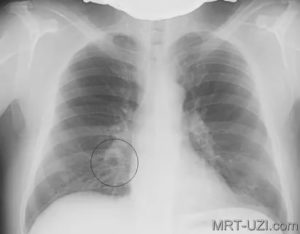

Чтобы диагностировать, нужно посмотреть фото, как выглядит на снимке рентгена пневмония очаговой формы. Также нужно быть ознакомленным с расшифровкой:

- наличие активного инфильтрата негомогенной структуры;

- «подозрительная» тень имеет нечеткое очертание;

- при воспалении плевры прослеживается линейная тяжистость, жидкость в реберно-диафрагмальном синусе на боку патологии;

- на фоне разрешения процесса место инфильтрации делается неоднородным за счет зон разрушения и заживления легких.

Данному виду патологии свойственно поражение небольших участков легочной ткани.

Изображение очаговой пневмонии прослеживается плохо, затемнения могут быть средней или вовсе слабой интенсивности.

Размеры очагов поражения в среднем достигают полутора сантиметров, при отсутствии лечения их количество увеличивается. На фото ниже изображен пример правосторонней очаговой пневмонии.

Очаговая форма болезни проявляется легким лейкоцитозом, незначительными хрипами при дыхании и гипертермией. На начальном этапе развития заболевания его следы можно не обнаружить на рентгеновском снимке. Однако, опытный доктор может заподозрить заболевание по следующим косвенным признакам, видимым на снимках:

- Наличие теней.

- Признаки плеврита на рентгене.

- Увеличение размеров корня легкого.

- Нарушение структуры рисунка легочной ткани.

- Очаговая форма. На рентгене отображаются небольшие (1-1,5 см) тени со слабой или умеренной интенсивностью окраски, неоднородной структурой и нечеткими границами. Очаги поражения могут быть единичными или множественными, а в некоторых случаях они сливаются в одно большое пятно. Корни легких расширены, причем нарушения нормального рисунка органа могут сохраняться в течение нескольких дней после выздоровления.